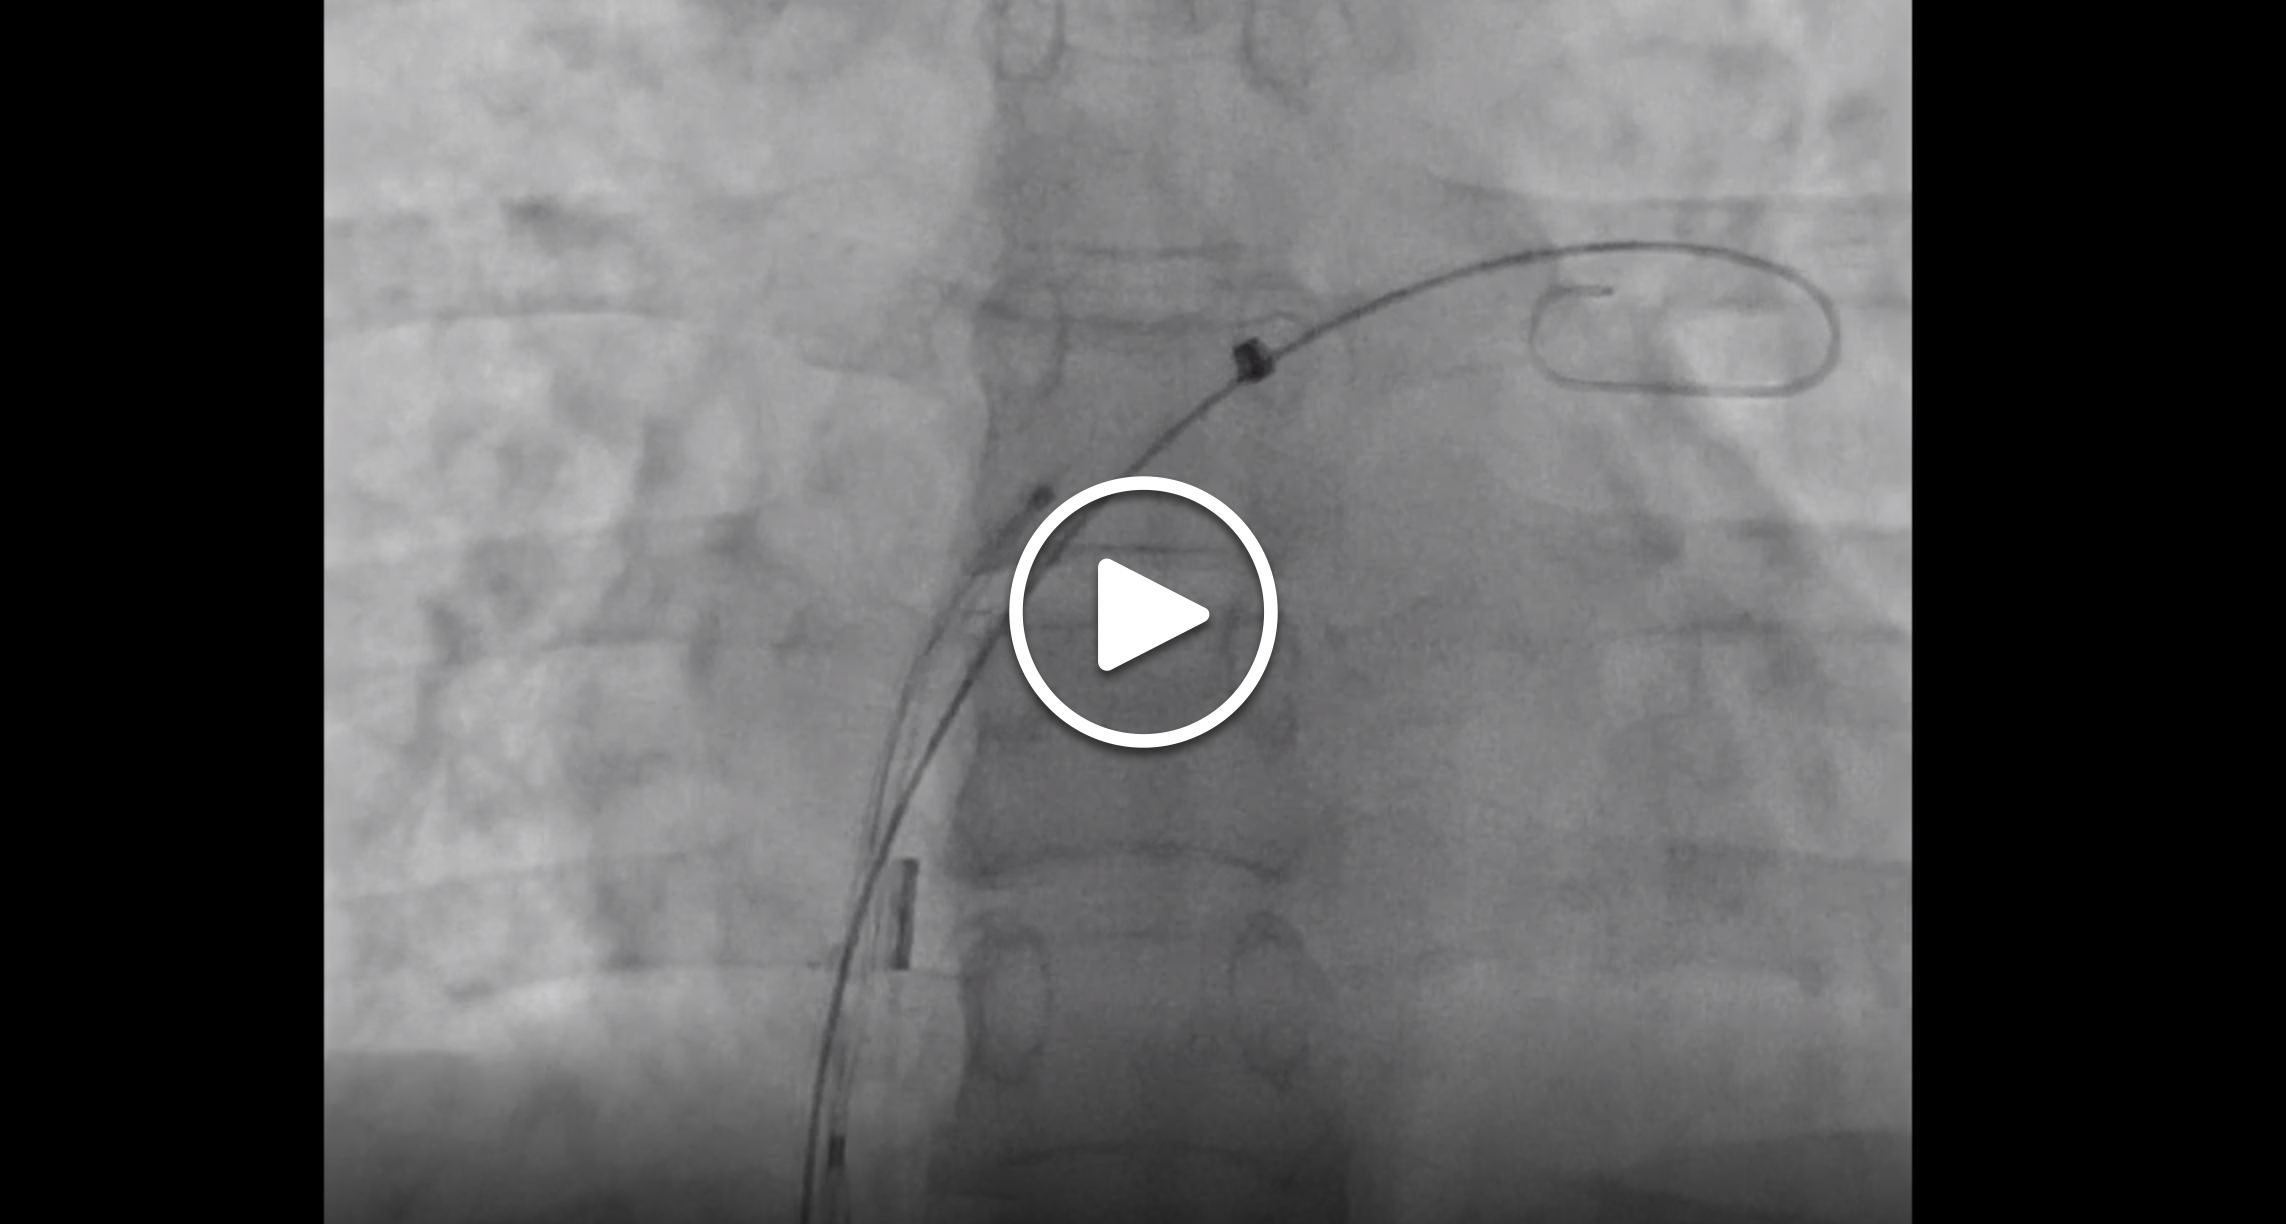

We then cross the PFO using a Goodale-Lubin catheter (Medtronic) and a straight Amplatz wire (Cook Medical) in the long-axis view. Under fluoroscopy, we exchange the straight wire with a J-tip Amplatz Extra Stiff wire (Cook Medical), which is then advanced and parked in the left superior pulmonary vein.

We advance the deaired device delivery system over the Amplatz Extra Stiff wire into the left atrium and then remove the Amplatz Extra Stiff wire. The Cardioform septal occluder is typically preloaded into the delivery system, which minimizes the risk of air embolism. However, it is essential to maintain a wet-to-wet connection and avoid deep inspiration when an Amplatzer device is loaded into the delivery system because these situations carry a higher risk of air embolism. Once the device is advanced into the left atrium, the left-sided disc is unsheathed and pulled against the septum (Figure 1D). While maintaining a slight tug on the system, the right-sided disc is unsheathed/deployed, allowing the device to fully bracket the PFO.

The position and seal of the device are confirmed by two-dimensional and color Doppler ICE imaging in the short- and long-axis views. Device-specific securing mechanisms are then applied (tug test for Amplatzer and loop locking for Cardioform), and further evaluation with ICE is performed (Figure 1E and 1F). When satisfactory position, stability, and seal are ensured, the device is released under ICE and fluoroscopic guidance. The procedure is concluded by a final ICE survey with a clockwise sweep of the probe, starting at the home view to rule out pericardial effusion. Hemostasis can be achieved with a figure-of-eight 0 silk suture and additional manual pressure for 5 minutes.